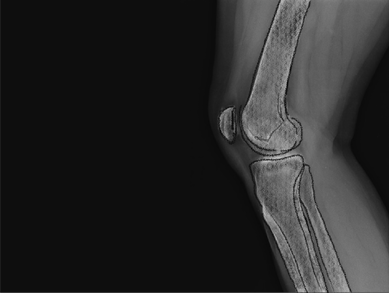

Total knee replacement

Experience the benefits of robotic knee replacement, offering accuracy and improved joint function for long-term relief.

Partial knee replacement

Targeted robotic surgery for partial knee replacement, preserving healthy tissue while relieving pain and restoring movement.